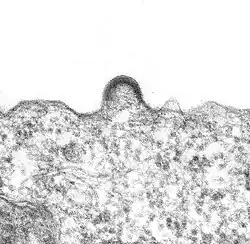

En 1983, Robert Gallo n'est pas parvenu à isoler le virus dans les échantillons sanguins de patients atteints du sida. Willy Rozenbaum pense alors que chez les malades du sida, la plupart des cellules infectées sont détruites et que c'est la raison du manque de résultats dans ces tentatives d'isolement du virus. Il a alors l'idée de chercher le virus dans un organe riche en lymphocytes, les ganglions lymphatiques de personnes malades mais qui ne sont pas encore en phase de sida. En janvier 1983, Willy Rozenbaum prélève un échantillon d'un patient atteint d'une lymphadénopathie, pathologie identifiée comme une maladie opportuniste du stade pré-sida. L'échantillon est mis en culture et Françoise Barré-Sinoussi découvre une activité de transcriptase inverse, confirmant la présence d'un rétrovirus. Une apoptose apparaît et l'adjonction de globules blancs à la mise en culture relance alors l'activité de transcriptase inverse. Un examen au microscope électronique a permis de visualiser, pour la première fois, le virus[8], le 4 février 1983.

La capside sort de la cellule infectée en arrachant une partie de la membrane cellulaire (à laquelle ont été préalablement fixées les protéines virales de surface (gp120 et gp41)).